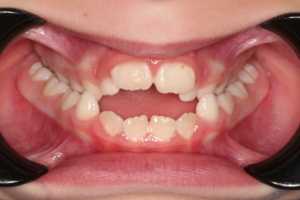

Когда половинки челюсти расходятся, на месте шва начинает образовываться свободное пространство. Постепенно оно заполняется новообразовавшейся костной тканью, которая костенеет и не позволяет в будущем двум половинкам принять прежнее положение. В процессе расширения нёба, между зубными единицами начнёт образовываться свободное пространство. Особенно это заметно между передними резцами. Этого не избежать. Решается проблема дальнейшей корректировкой брекетами (или иными ортодонтическими конструкциями).

1. Резкое сужение верхней челюсти

2. Большой дефицит места для постоянных зубов

Показания к использованию ортодонтического аппарата Хааса:

- Скученное положение резцов

- Сужение верхней челюсти

- Двухсторонний перекрестный прикус